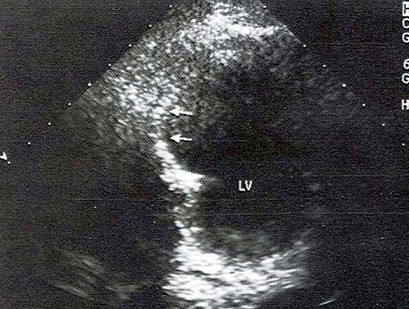

哪个是该病例最可能的诊断()。

A、真性室壁瘤

B、假性室壁瘤

C、室壁憩室

D、扩张型心肌病

E、膜部瘤

真性室壁瘤(室壁瘤)与假性室壁瘤的主要区别在于()。

A、室壁局部有膨出

B、室壁运动呈矛盾运动

C、室壁变薄

D、瘤壁与室壁是否有连续性

E、真性室壁瘤的内层为心内膜,而假性室壁瘤为心肌组织或心包